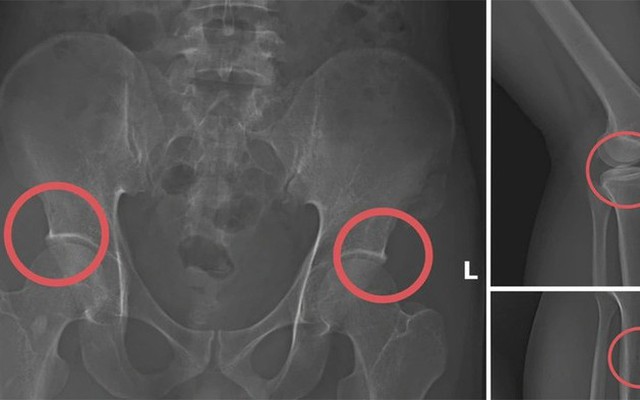

Cựu cán bộ y tế cầm đầu đường dây tự đánh vỡ xương trục lợi 6 tỷ đồng bảo hiểm

Pháp luật 2025-11-14T19:46:00Tạ Minh Châu tiêm thuốc mê, dùng búa tác động vào xương tạo nên các vết nứt, vỡ xương rồi dựng hiện trường giả điện giật, trượt chân ngã nhằm trục lợi bảo hiểm.